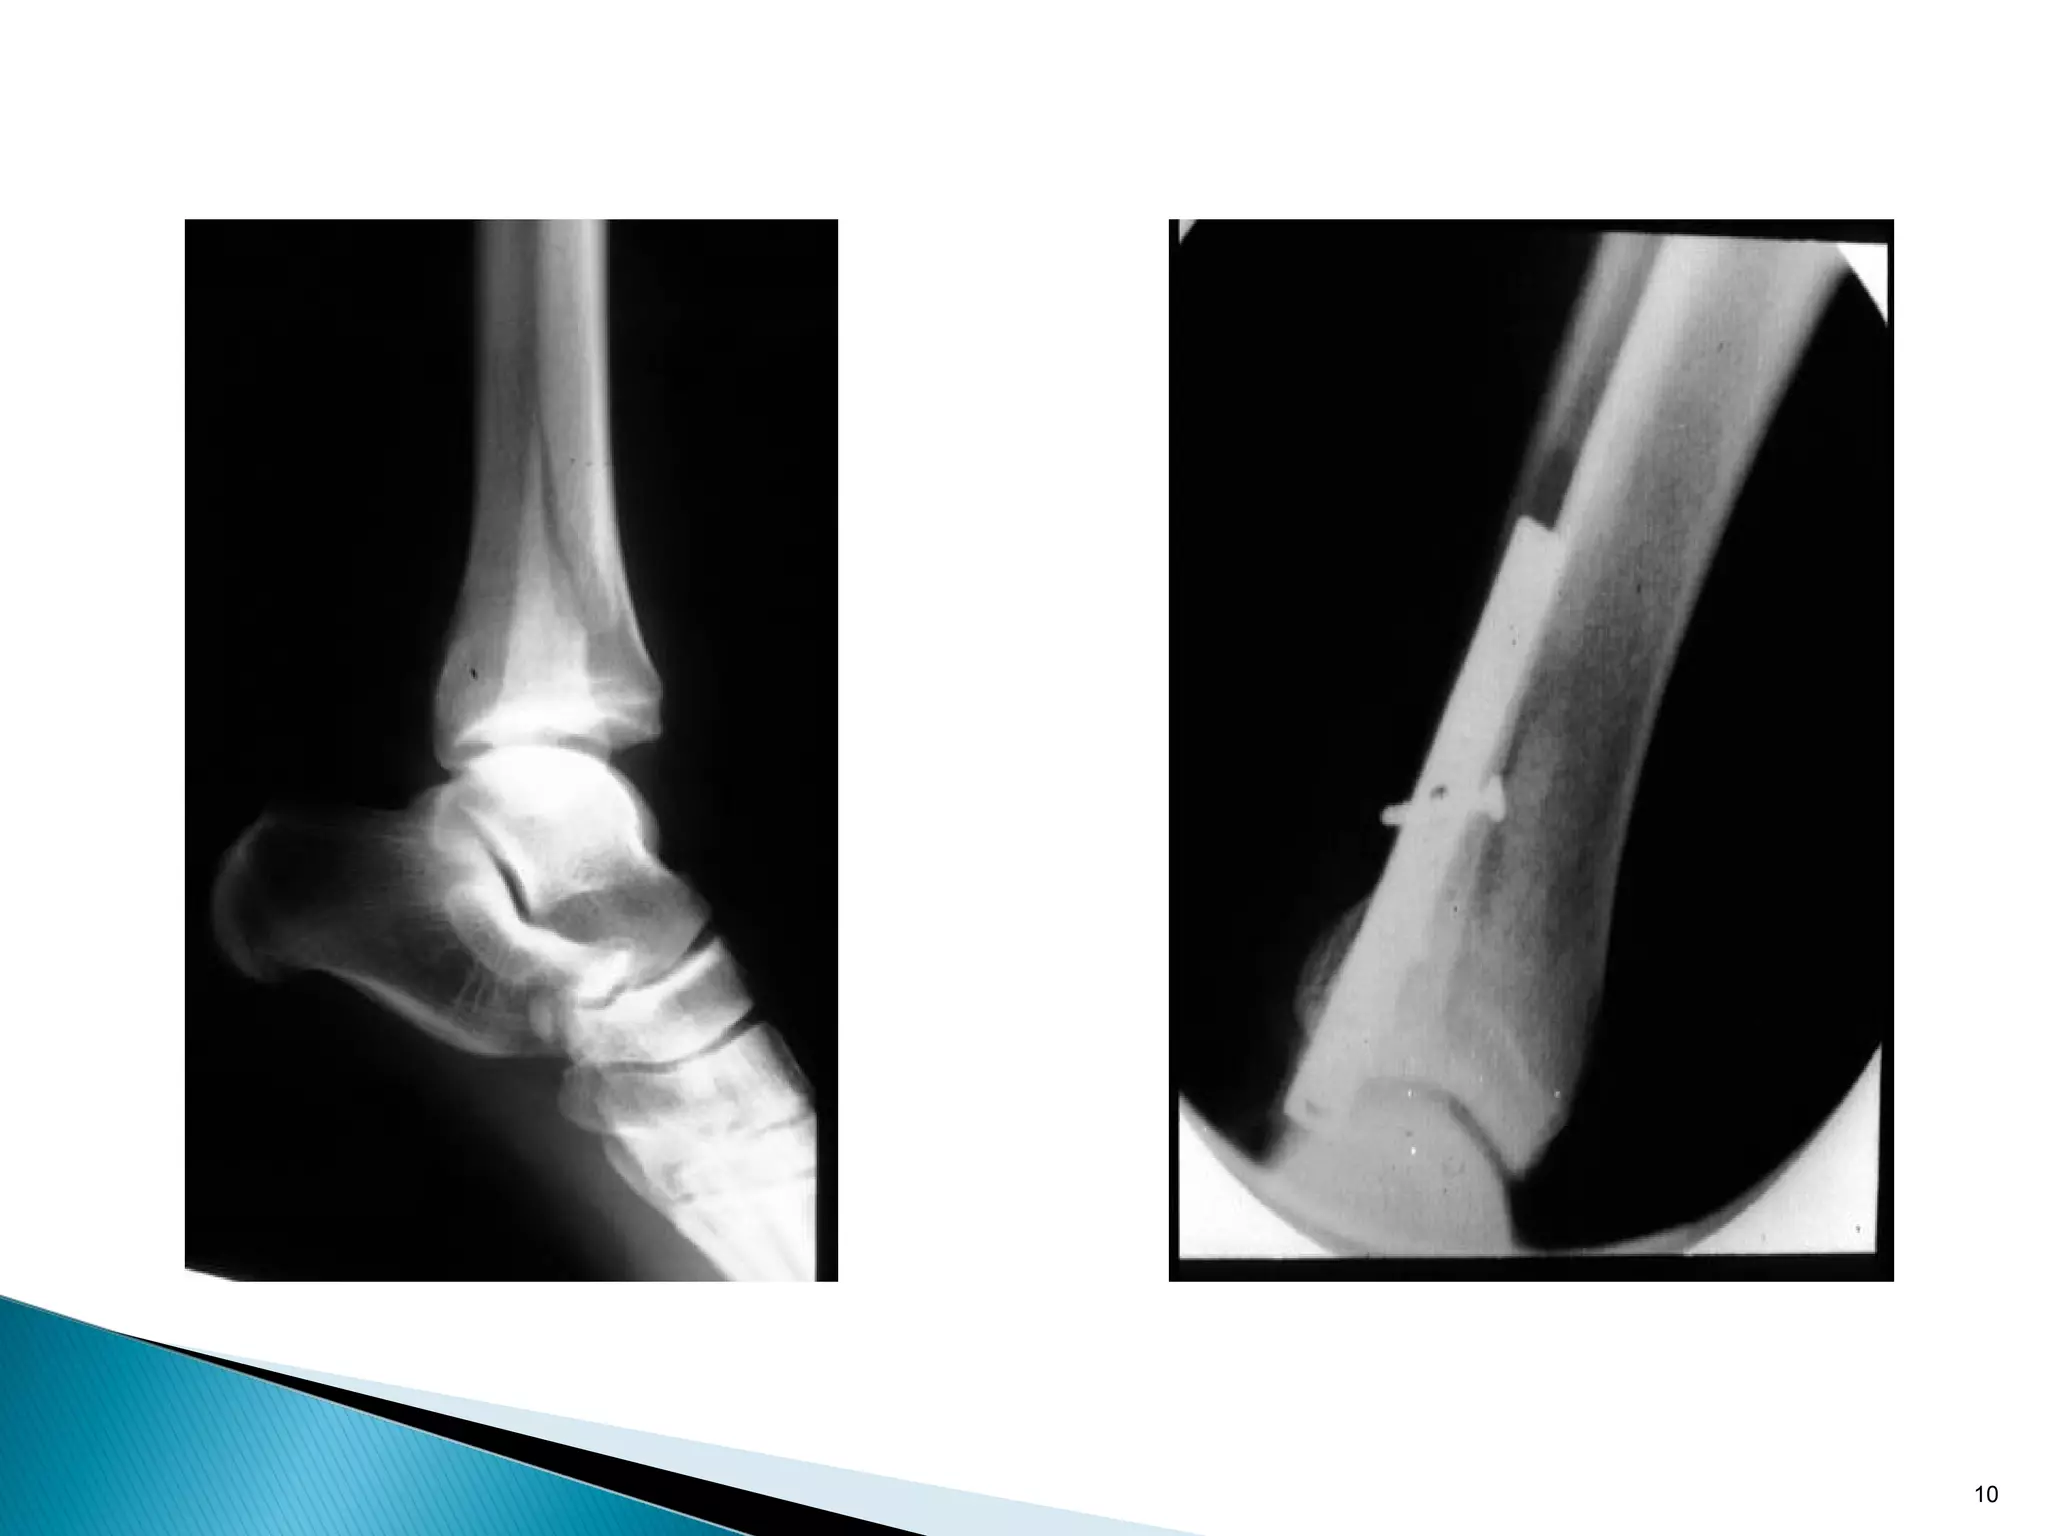

• Reduces torsional and axial forces on interfragmentary

compression screw(s)

• Always used with lag screws

• Requires anatomical reduction

9

10

• Reduces torsionaland axial forces on interfragmentary compression screw(s) • Always used with lag screws • Requires anatomical reduction 9